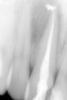

Михалыч007 Опубликовано 24 мая, 2012 Поделиться Опубликовано 24 мая, 2012 ещё одномоментная пломбировка зуба гуттаперчей Ссылка на комментарий